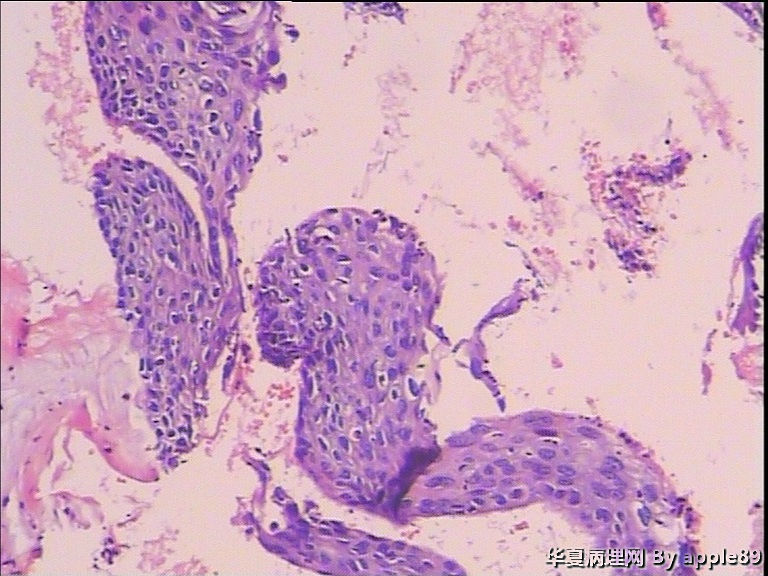

患者40岁,妇科门诊体检病人,无病史

×参考诊断

12、13图可以看到角化不良细胞及高核浆比的异常鳞状细胞,还有一些图也可以看到问题细胞,很多的细胞珠存在,应该是ASC-H,阴道镜+宫颈活检

裸核很多,染色质细腻均匀,异型性不大;另外还可以看到宫颈管细胞、双核细胞,有个别细胞内还可以看到角化珠;总体给人的直觉是没有问题,但是图10、13会让你感觉不是很放心,不能放过此例,ASC-US。

ASC-H,图24那样的细胞不放心,要么没问题,有问题都可能是个鳞癌。

hsil-scc

少数细胞有异型、梭性,和不清楚的角化珠,可以考虑“高度病变”。

细胞学报告:HSIL

这例我报的HSIL,建议阴道镜活检,后来病人活检了,图片如下,组织有点碎,片子刚做好我就拿出来采图了,也许补切过后会更好看点

这个病人活检的片子补切后我会再看看,必要的话再采几张图上来,TCT看到很多角化珠样的东东,但是活检一点都没有,不知道是没有钳到还是没切到还是本来就没有。如果这个病人有进一步的治疗如leep刀的话,我会继续关注。